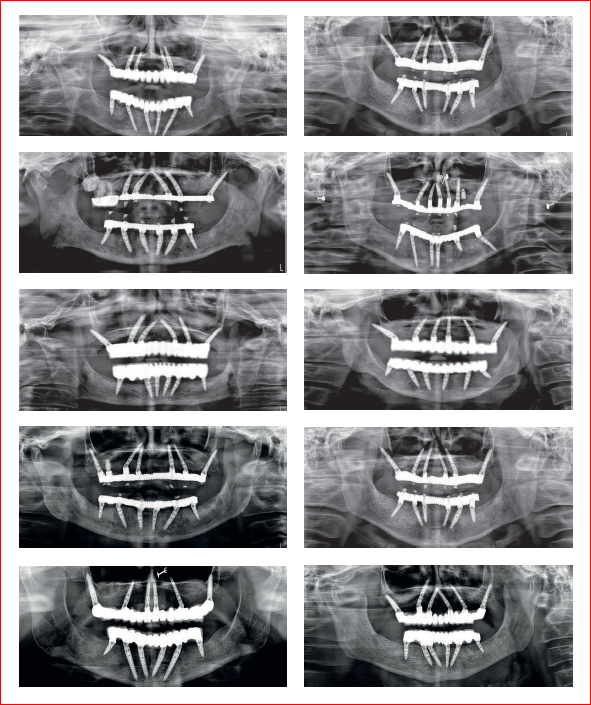

CASESKORTICALE TPR IMPLANTS

KORTICALE TZG IMPLANTS

KORTICALE BL/ SP IMPLANTS